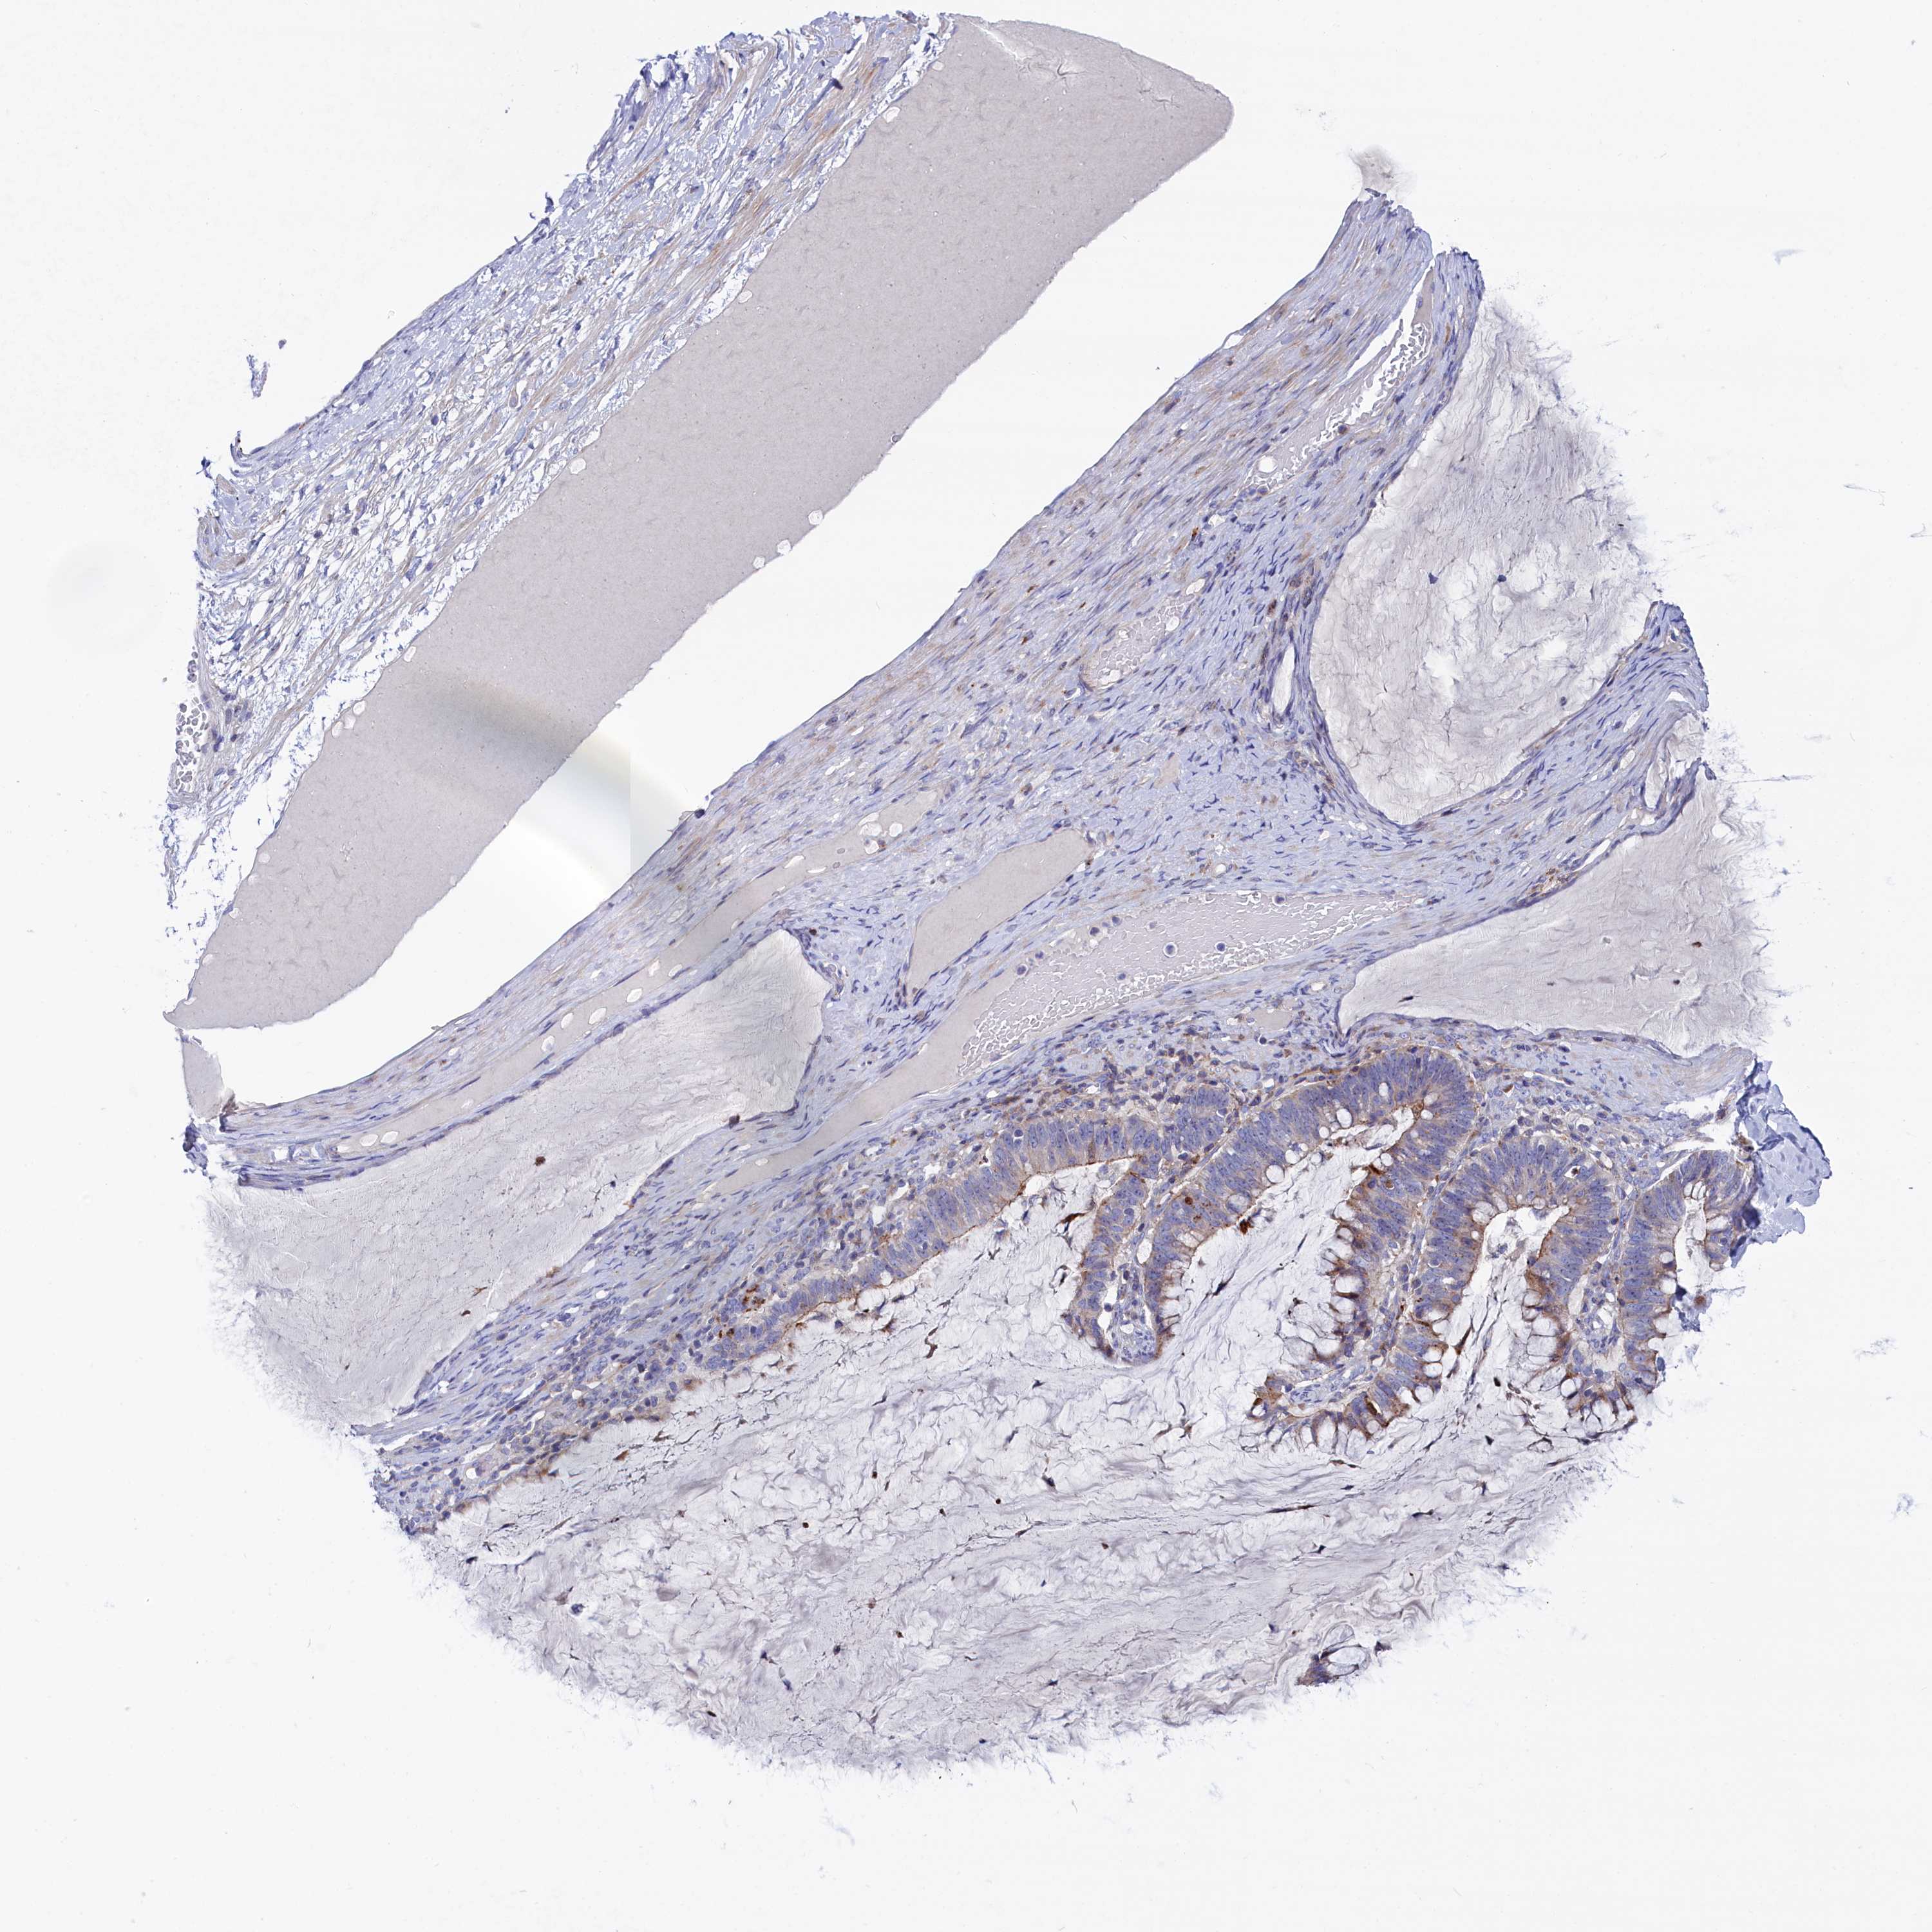

OVARIAN CANCER - Protein expressioni

A mouse-over function shows sample information and annotation data. Click on an image to view it in a full screen mode. Samples can be filtered based on level of antibody staining by selecting one or several of the following categories: high, medium, low and not detected. The assay and annotation is described here.

Note that samples used for immunohistochemistry by the Human Protein Atlas do not correspond to samples in the TCGA dataset.

Antibody stainingi

Antibody staining in the annotated cell types in the current human tissue is reported as not detected, low, medium, or high, based on conventional immunohistochemistry profiling in selected tissues. This score is based on the combination of the staining intensity and fraction of stained cells.

Each image is clickable and will lead to virtual microscopy that enables deeper exploration of all samples and also displays staining intensity scores, fraction scores and subcellular localization as well as patient and tissue information for each sample.

Antibody HPA042042

Cystadenocarcinoma, serous, NOS

Carcinoma, endometroid

Cystadenocarcinoma, mucinous, NOS

Carcinoma, NOS